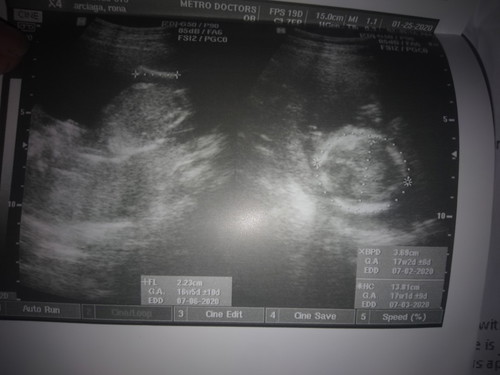

Sino po marunong tumingin dito yung alam san yung ulo ni baby?

Yung head po ni baby ay yung nasa right side. Un lagi sinusukat ng ob ko na head part ni baby para malaman kung ilang weeks ung size ni baby

yung bilog na may dot dot yan yung ulo at sinusukat ng ultrasoundyl yung size ng ulo ng baby mo